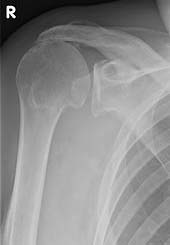

Die Röntgenuntersuchung ist erst in fortgeschrittenen Stadien der Rotatorenmanschettenruptur aussagekräftig. Sie zeigt ein Höhertreten des Oberarmkopfes. Auch Veränderungen am Oberarmkopf durch den veränderten Druck stellt das Röntgen dar.